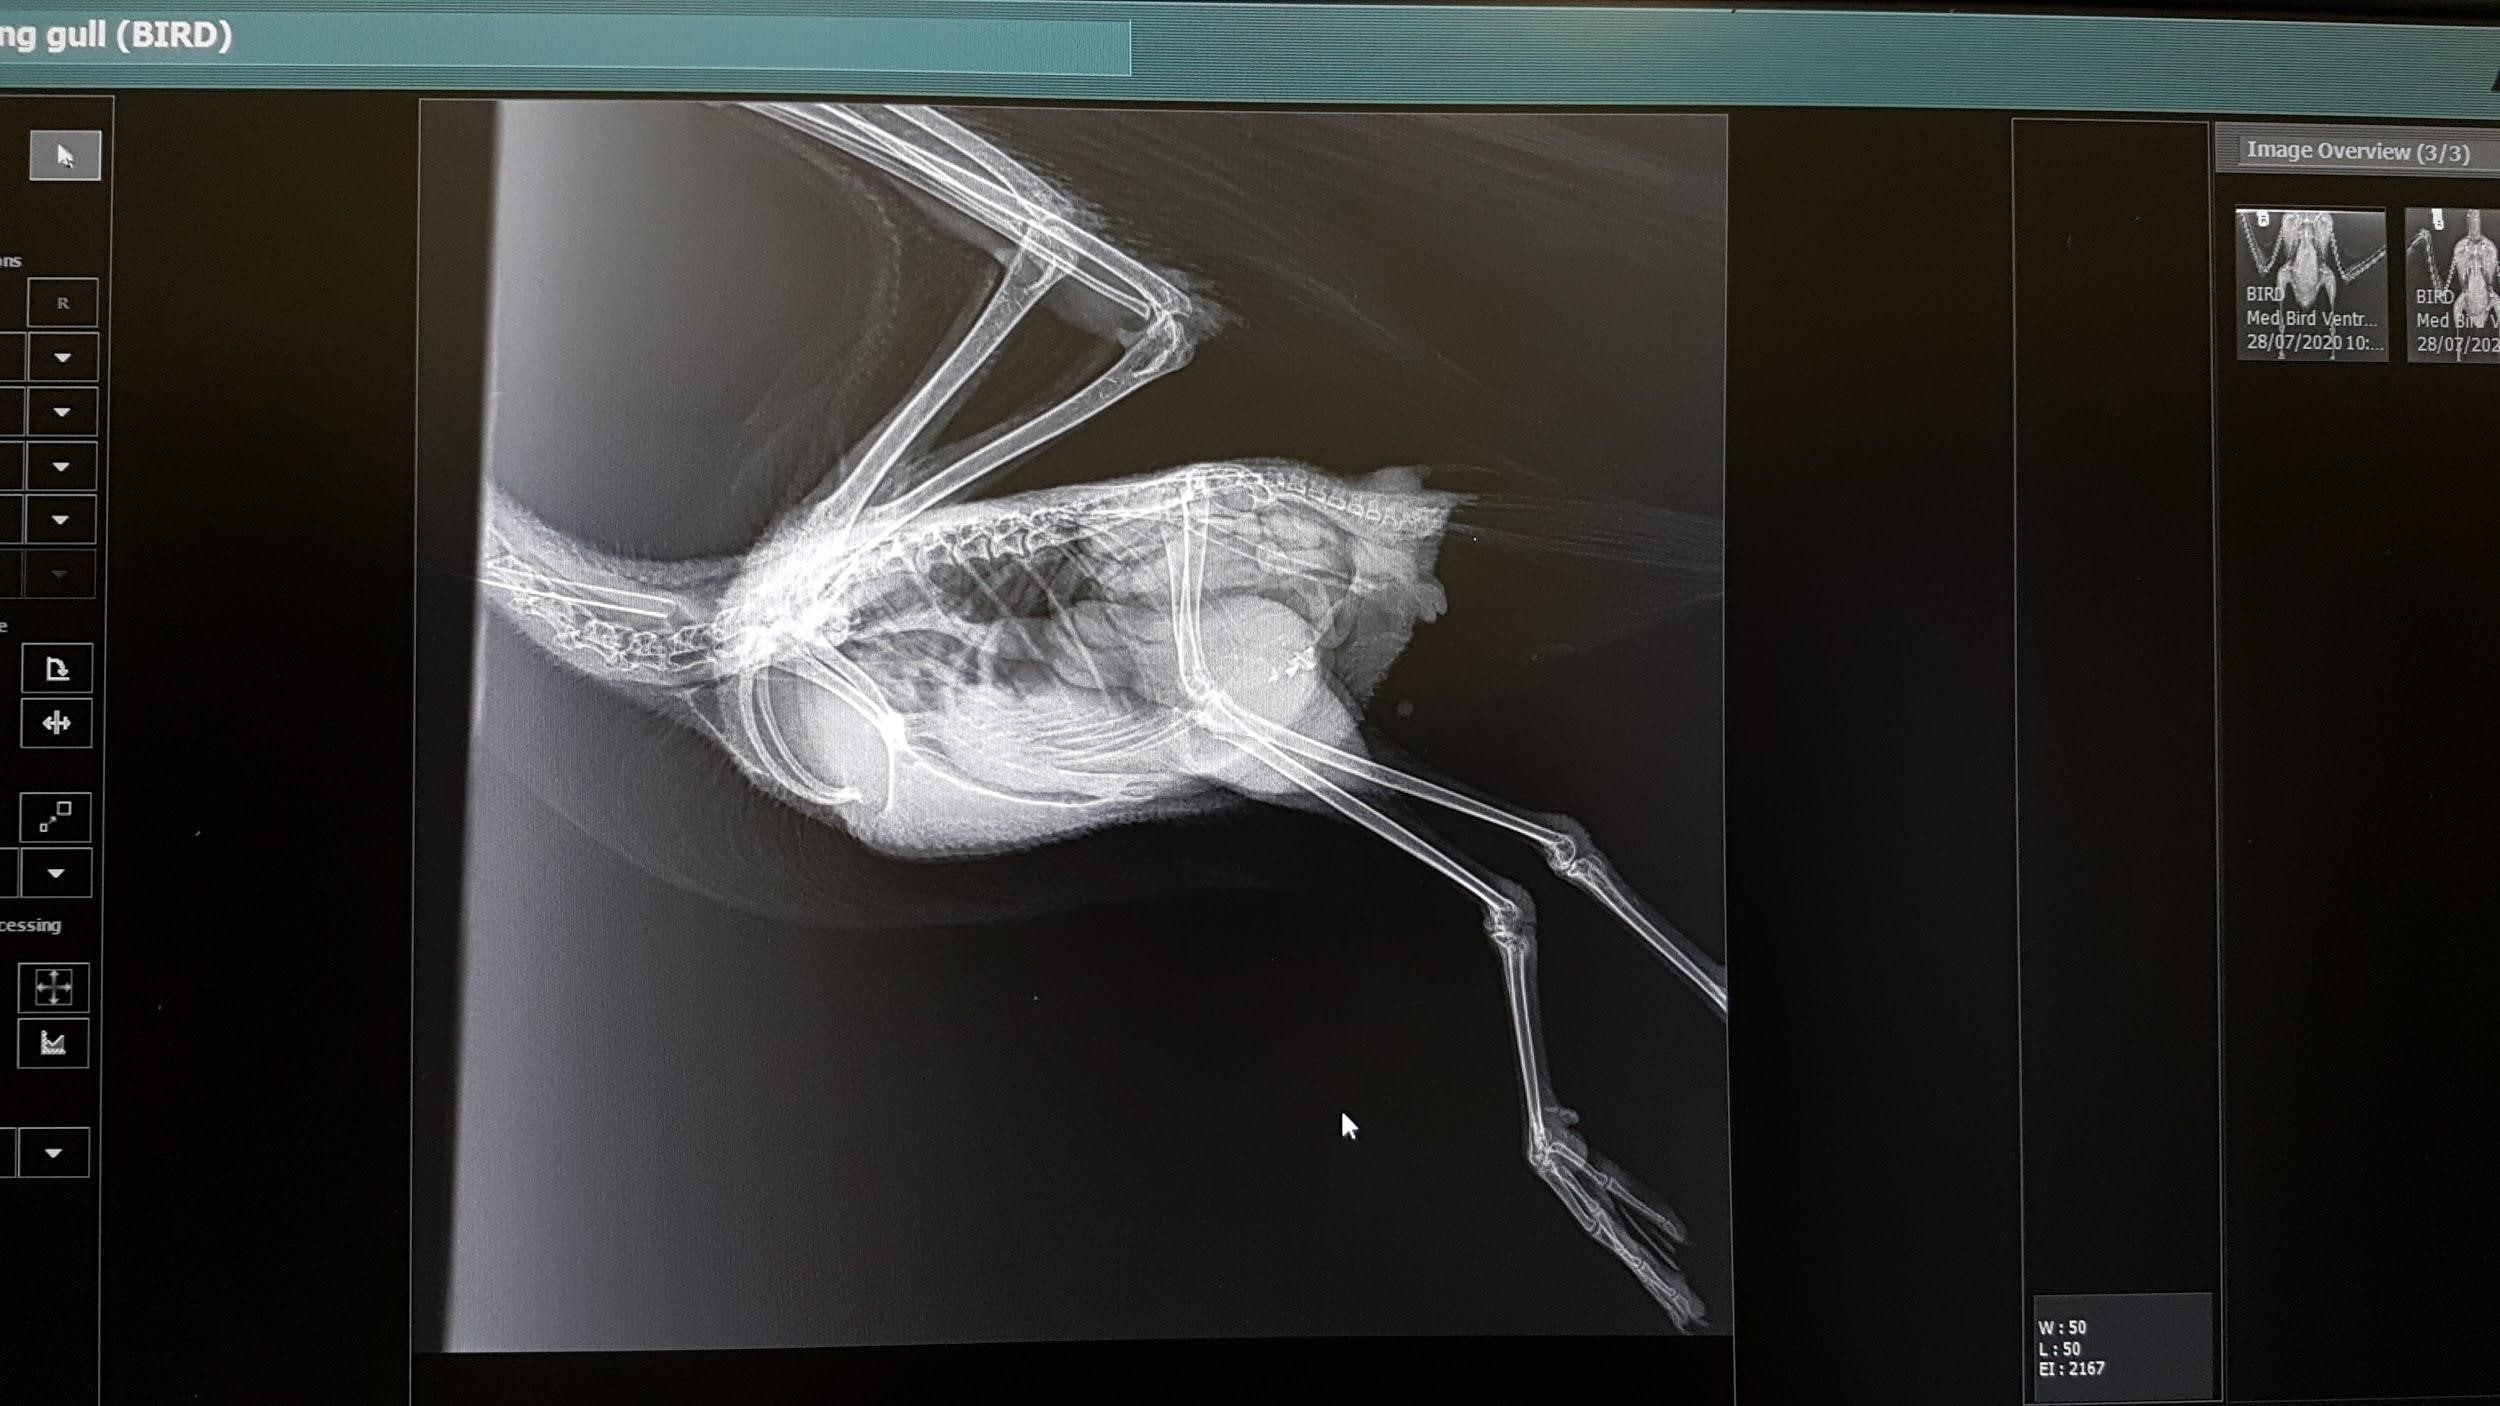

Avian radiology

Lateral Coelomic View

(1) It is recommended to obtain both lateral and VD views to aid diagnosis.

(2) Place the bird on it’s left or right side on the plate

(3) Extend the wings dorsally above the body

(5) Secure the wings to the plate by placing micropore or durapore tape across the primaries. The wings should be superimposed on each other or only slightly apart.

(6) Secure the legs to the plate using tape with the upper leg slightly more cranial than the lower leg.

(7) The keel should be parallel to the plate.